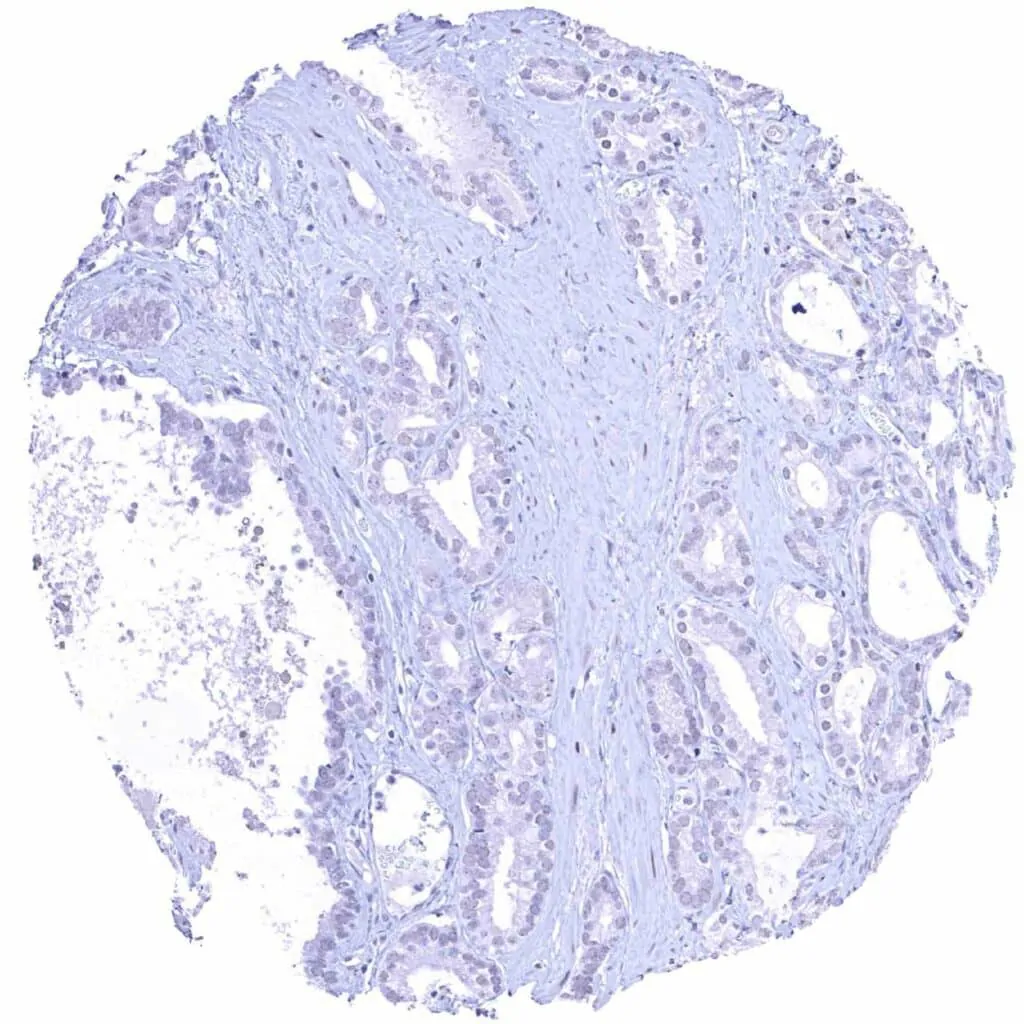

Breast – Invasive breast cancer of no special type (NST) with faint Cyclin E1 immunostaining of few tumor cells